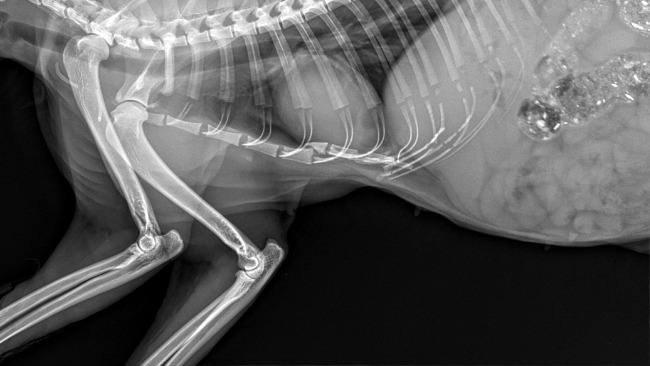

Kotka została znaleziona na terenie jednej z firm w Steszewie, gdzie przyszła po pomoc po potrąceniu przez samochód. Kotka ma problemy z chodzeniem na tylnych nóżkach, momentami ciągnie nogi za sobą a w najlepszym wypadku chodzi chwiejąc się na boki, często potykając się.

Podczas badania USG było podejrzenie ropomacicza, więc konieczna była pilna sterylizacja. Okazało się, że dziewczyna miała ogromną cystę na jajniku ale na szczęście nie było ropomacicza. Niestety zabieg pogorszył jej stan i chodzi po nim bardziej chwiejnie, a jej tylne nóżki często odmawiają posłuszeństwa.

Zosia była na konsultacji u najlepszego ortopedy w Poznaniu, który dostrzegł złamanie mostka i zalecił rehabilitację a po jej zakończeniu zostanie oceniona czy kwalifikuje się do operacji. W opłaceniu wizyt pomogła Gmina Stęszew, jedna z fundacji i dom tymczasowy. Niestety potrzebne są pieniądze na rehabilitację, gdyż są to duże koszty a jedna wizyta to koszt nawet ok 100 złotych. Zosia powinna mieć ok 10 zabiegów. W tym nie pomoże już Gmina, bo rehabilitacja bezdomnego kota nie jest w ich zakresie pomocy... Fundacja jedyna która pomogła i zareagowała na prośbę o pomoc- wizyta u Ortopedy była 2 listopada i od tamtej pory nic nie udało się zorganizowac a Zosia nie powinna czekac bo ma to wpływ na jej sprawność.